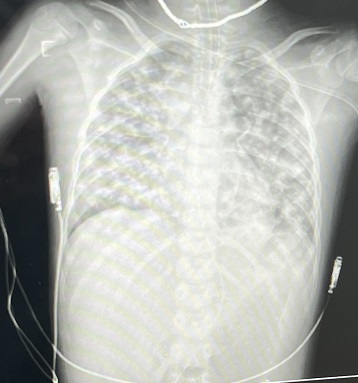

Phim chụp phổi bệnh nhân trắng xoá thời điểm mới vào viện (Ảnh: BVCC)

Bác sĩ Nguyễn Hữu Hiếu - Trung tâm Nhi khoa, Bệnh viện Bạch Mai cho biết, ngay khi nhập viện, bệnh nhi được đặt máy thở không xâm nhập, đặt ống nội khí quản và thở máy, tuy nhiên bệnh nhi bị xuất huyết phổi nhiều, phổi chụp lên mờ lan tỏa 2 bên trường phổi. Bệnh nhi rơi vào tình trạng suy hô hấp, sốc nhiễm khuẩn nặng, mạch nhanh, huyết áp tụt...